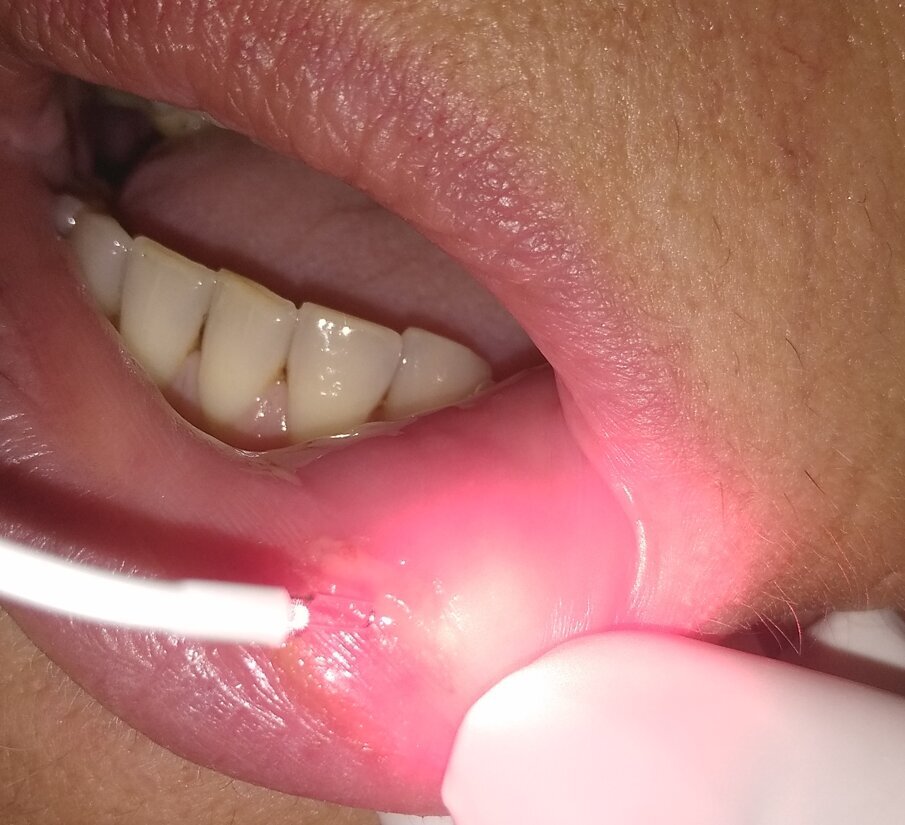

Una paziente di 58 anni era giunta alla nostra osservazione per una grossa ulcera labiale di circa 1,3 cm. La paziente aveva eseguito una estrazione 2 giorni prima. All’anamnesi nessuna patologia particolare è stata rilevata. L’anestesia per la chirurgia precedente era durata diverse ore, e la paziente stessa, che normalmente tende a “mordicchiare” il labbro, non consapevole della forza masticatoria, in quanto ancora sotto anestesia, aveva determinato una lacerazione dei tessuti labiali, e la diagnosi era stata di ulcera traumatica (Fig. 5). Vista la difficoltà della paziente di apporre una terapia topica in un tessuto molto dolorante, si è deciso di provare a desensibilizzare con luce laser a diodi 660 nm, 100 mwatt, per 5 minuti, lo stesso dispositivo utilizzato nel caso precedente (Fig. 6), nell’ottica della Low Level Laser Therapy (LLLT). Subito dopo la seduta la paziente ha mostrato un grosso sollievo e a 5 giorni la paziente era guarita completamente (Fig. 7).